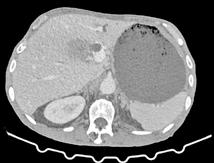

A las 36 horas de vida presenta nuevo empeoramiento respiratorio, se solicita estudio completo y se realiza punción lumbar (a pesar de paráme tros infecciosos negativos en la analítica). Se obtiene líquido purulento y se procede a escalada de tratamiento a ceftriaxona y ampicilina (mantiene tratamiento durante 7 y 3 días respectivamente, no aislándose microorga nismos en muestras de líquido cefalorraquídeo ni hemocultivos). Se repite la radiografía de tórax en la que se evidencia neumotórax de nueva apa rición e imagen sugestiva de neumomediastino. Ante estos hallazgos, se solicita TC de tórax que confirma el diagnóstico y descarta la existencia de causas desencadenantes (Figura 2). Se mantienen requerimientos de VMNI durante 4 días más, siendo finalmente posible la desescalada gradual a oxigenoterapia con gafas nasales durante 4 días. Se consigue retirada del soporte respiratorio de manera completa pasados 8 días, realizando un control con TC de tórax a los 9 días de vida (Figura 3) que muestra mejoría significativa acompañándose de una recuperación clínica completa.

Figura 2. (Izq.) radiografía de tórax en proyección AP a las 36 horas de vida donde se objetiva neumotórax de nueva aparición (flechas azules) y una zona de hiperclaridad alrededor de la silueta cardíaca que sugiere importante neumomediastino (estrellas amarillas). (Der.) TC de tórax sin contraste intravenoso en ventana de pulmón que confirma la presencia de neumomediastino (estrella amarilla). Se objetivan focos de consolidación periféricos y bandas lineales de densidad aire paralelas y adyacentes a las vainas broncovasculares (flechas amarillas).